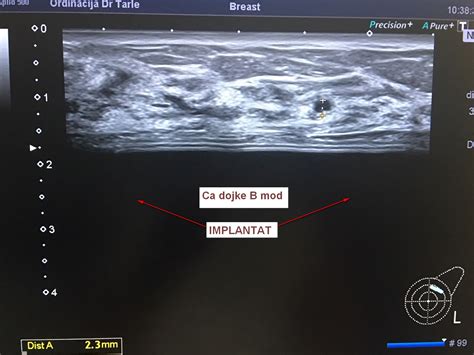

Sprva se je kot ginekolog v Mariboru posvečal pregledovanju dojk z ultrazvokom, vendar ga je kmalu pot vodila v strokovno usmeritev na področje umetne oploditve. To področje je bilo v tistem času še precej neznano in celo predmet posmehovanja, saj je le malo ljudi verjelo v njegov potencial. Kljub temu je dr. Vlaisavljević v tej novi smeri prepoznal neizmeren pomen za pomoč parom, ki se soočajo s težavami z zanositvijo.